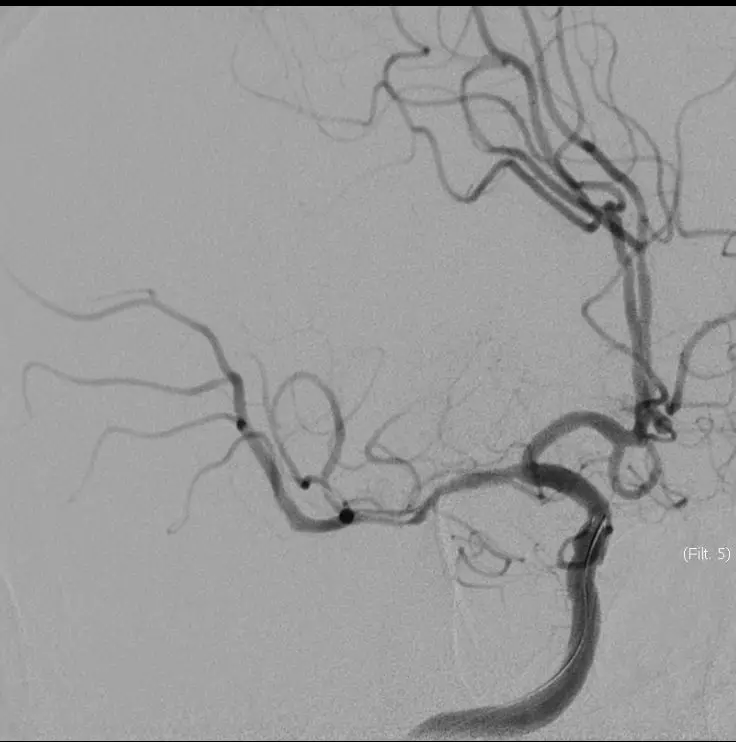

16:30分

手术结束

持续替罗非班4ml/H静脉泵入